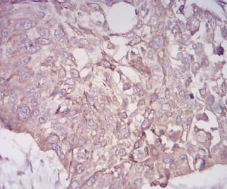

BMP7 Mouse Monoclonal antibody[6E5D]

IHC    1/200 - 1/1000